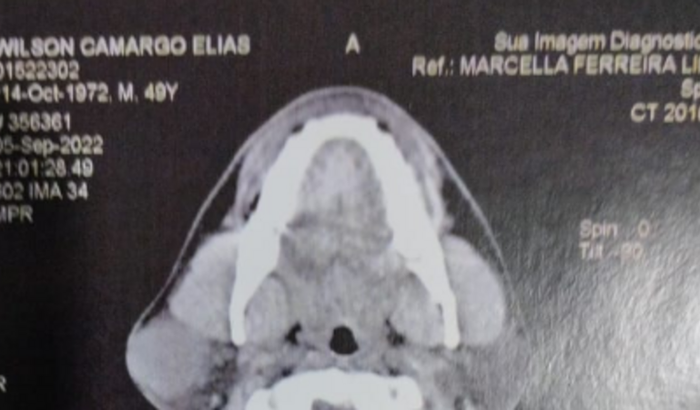

Meu nome é Wilson e tenho 51 anos. Estou com um abcesso na face direita que atualmente foi diagnosticado como paroditite (inflamação na glândula parótida, responsável pela saliva). Devido a situações de estresse, desemprego por 3 anos e o período pandêmico, ele acabou crescendo um pouco e agora estou na fila da cirurgia do SUS há 1 ano. Preciso fazer a cirurgia além de evitar futuras complicações, não complicar em próximos processos seletivos e cargos públicos de professor que estou concorrendo. Irei fazer a cirurgia com a equipe do Dr. Rafael DiCicco, especialista em cirurgia de cabeça e pescoço há mais de 20 anos. Agradeço de coração a atenção e ajuda!!